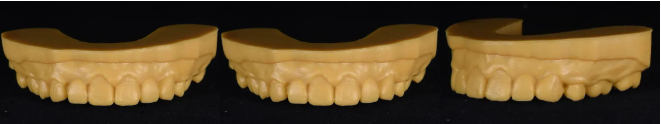

将二维效果转变成三维效果,设计13-23的美学效果,并打印出模型

在口内进行展示